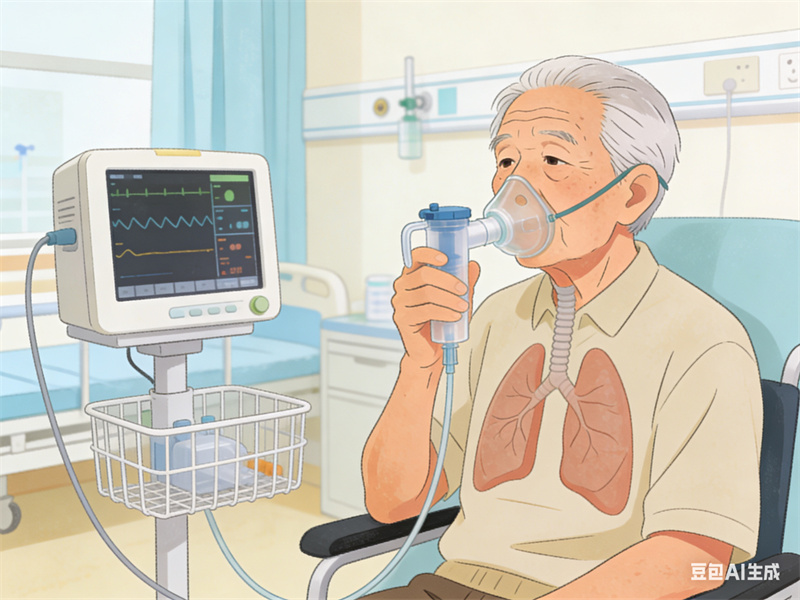

3.气短或呼吸困难:早期在劳力时出现,后逐渐加重,以致在日常活动甚至休息时也感到气短,是慢性阻塞性肺疾病的标志症状。

对于它的治疗主要包括药物治疗、调整生活方式、氧疗、康复训练等。常用的药物包括支气管扩张剂和吸入性皮质类固醇,通过缓解气道炎症和扩张气道,改善呼吸困难的症状。与此同时,戒烟、保持良好的空气质量、适度的身体锻炼都是非常重要的治疗策略。